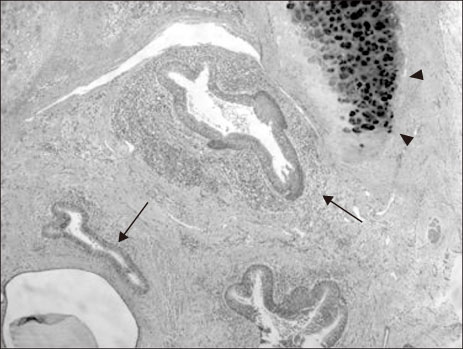

Fig. 1

Histologic findings of the resected congenital esophageal stenosis segment revealed respiratory epithelium (arrows) and cartilage (arrowheads) in the esophageal wall (H&E, ×40).

Fig. 1 Histologic findings of the resected congenital esophageal stenosis segment revealed respiratory epithelium (arrows) and cartilage (arrowheads) in the esophageal wall (H&E, ×40).